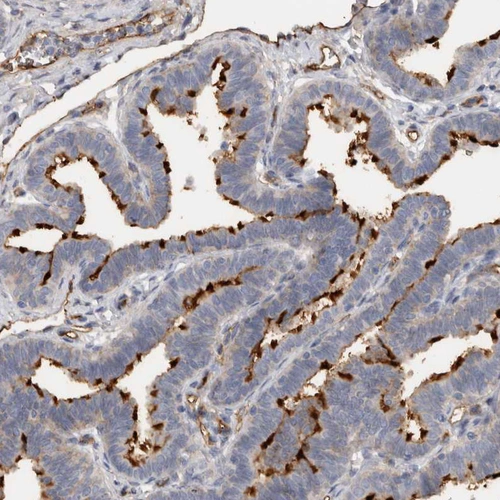

Immunohistochemical staining of human placenta shows strong membranous positivity in trophoblastic cells.